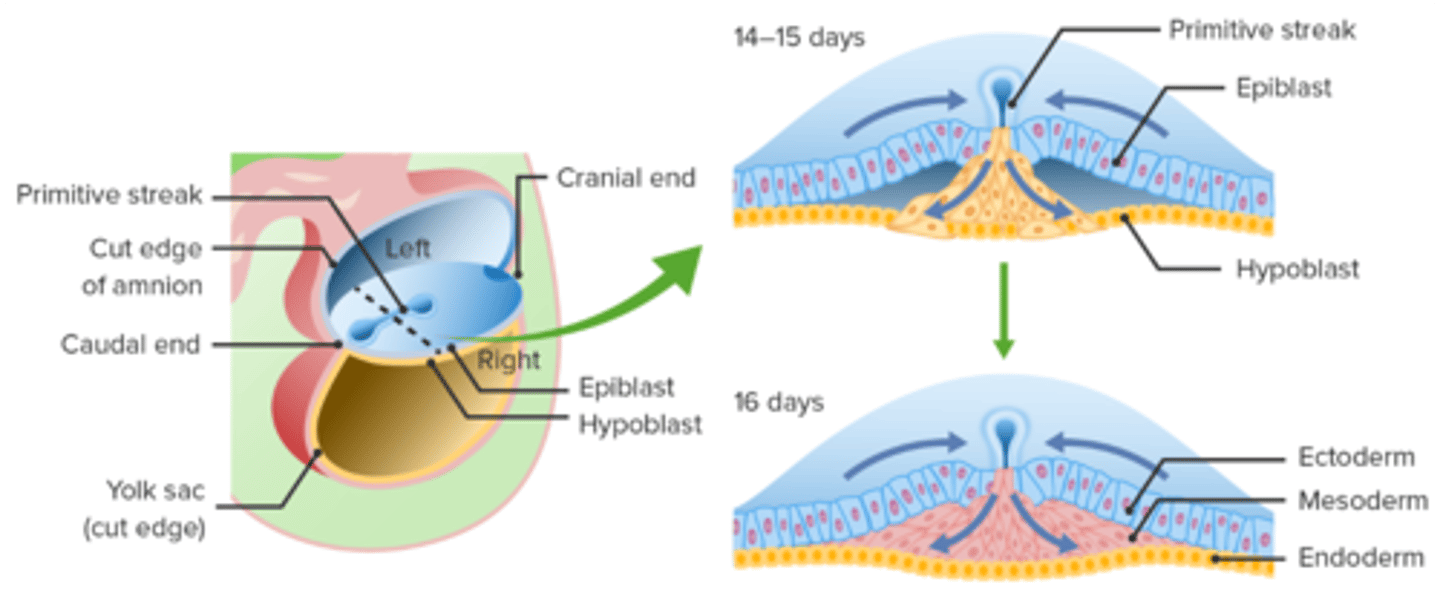

the (epiblast/hypoblast/trophoblast) is the source of all 3 germ layers. the 3 germ layers are established during _______________. describe how these layers are formed?

epiblast, gastrulation;

after a primitive streak forms on the epiblast, epiblast cells migrate toward the streak and invaginate into it to first create the endoderm, then the mesoderm. the ectoderm is the remaining cells in the epiblast.

which germ layer does the nervous system arise from?

ectoderm